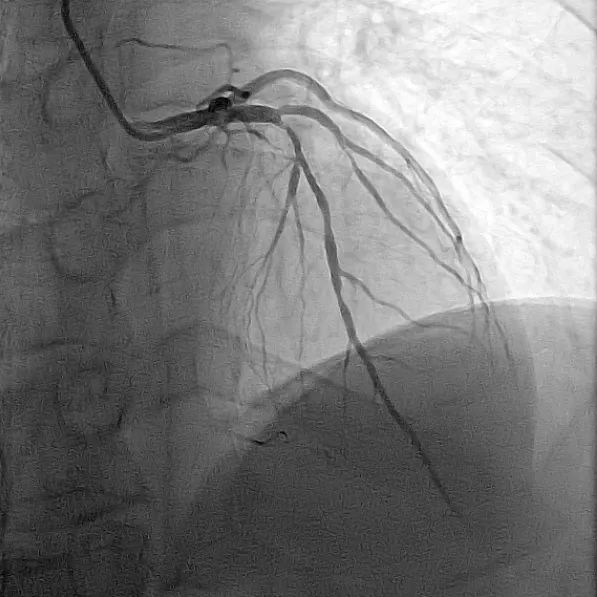

目前,唯邁醫(yī)療的DSA已裝機(jī)眾多三甲醫(yī)院,而剛剛完成裝機(jī)的濟(jì)南三院也在數(shù)日內(nèi)完成幾十例介入手術(shù),涵蓋經(jīng)介入造影治療,外周血管造影治療,心臟造影支架置入,滿足臨床多科室使用。

心臟造影

冠心?。?/span>介入治療可以恢復(fù)心臟的供血,減輕心肌缺血,緩解心絞痛癥狀。